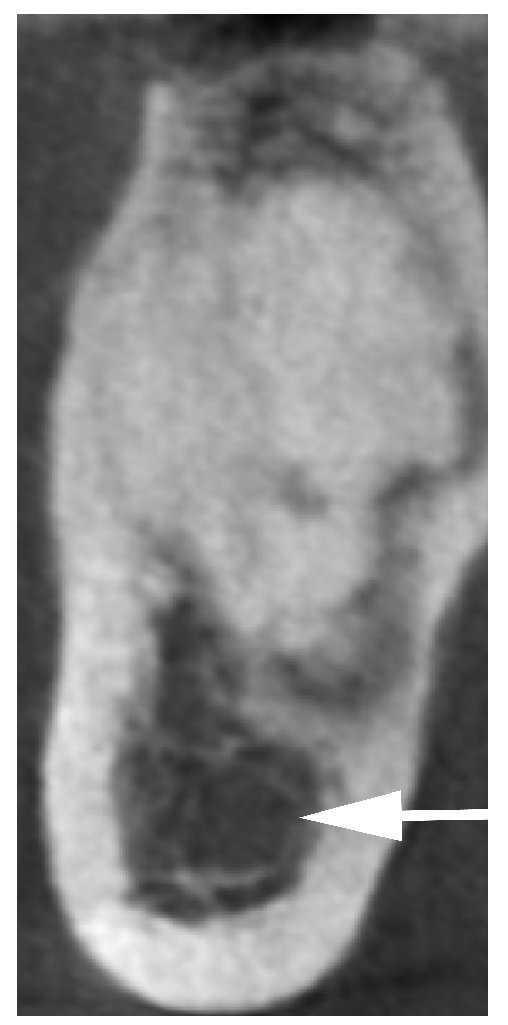

En el plano axial de la TVD se observa una masa hiperdensa y homogénea que ocupa casi toda la anchura de la porción alveolar. Dicha masa está rodeada por un borde hipodenso (figs. 2 y 3). En el plano vertical, se constata que la masa no está en contacto con el conducto dentario inferior del lado derecho (fig. 4).

Figura 2. Tomografía volumétrica digital dental: plano axial.